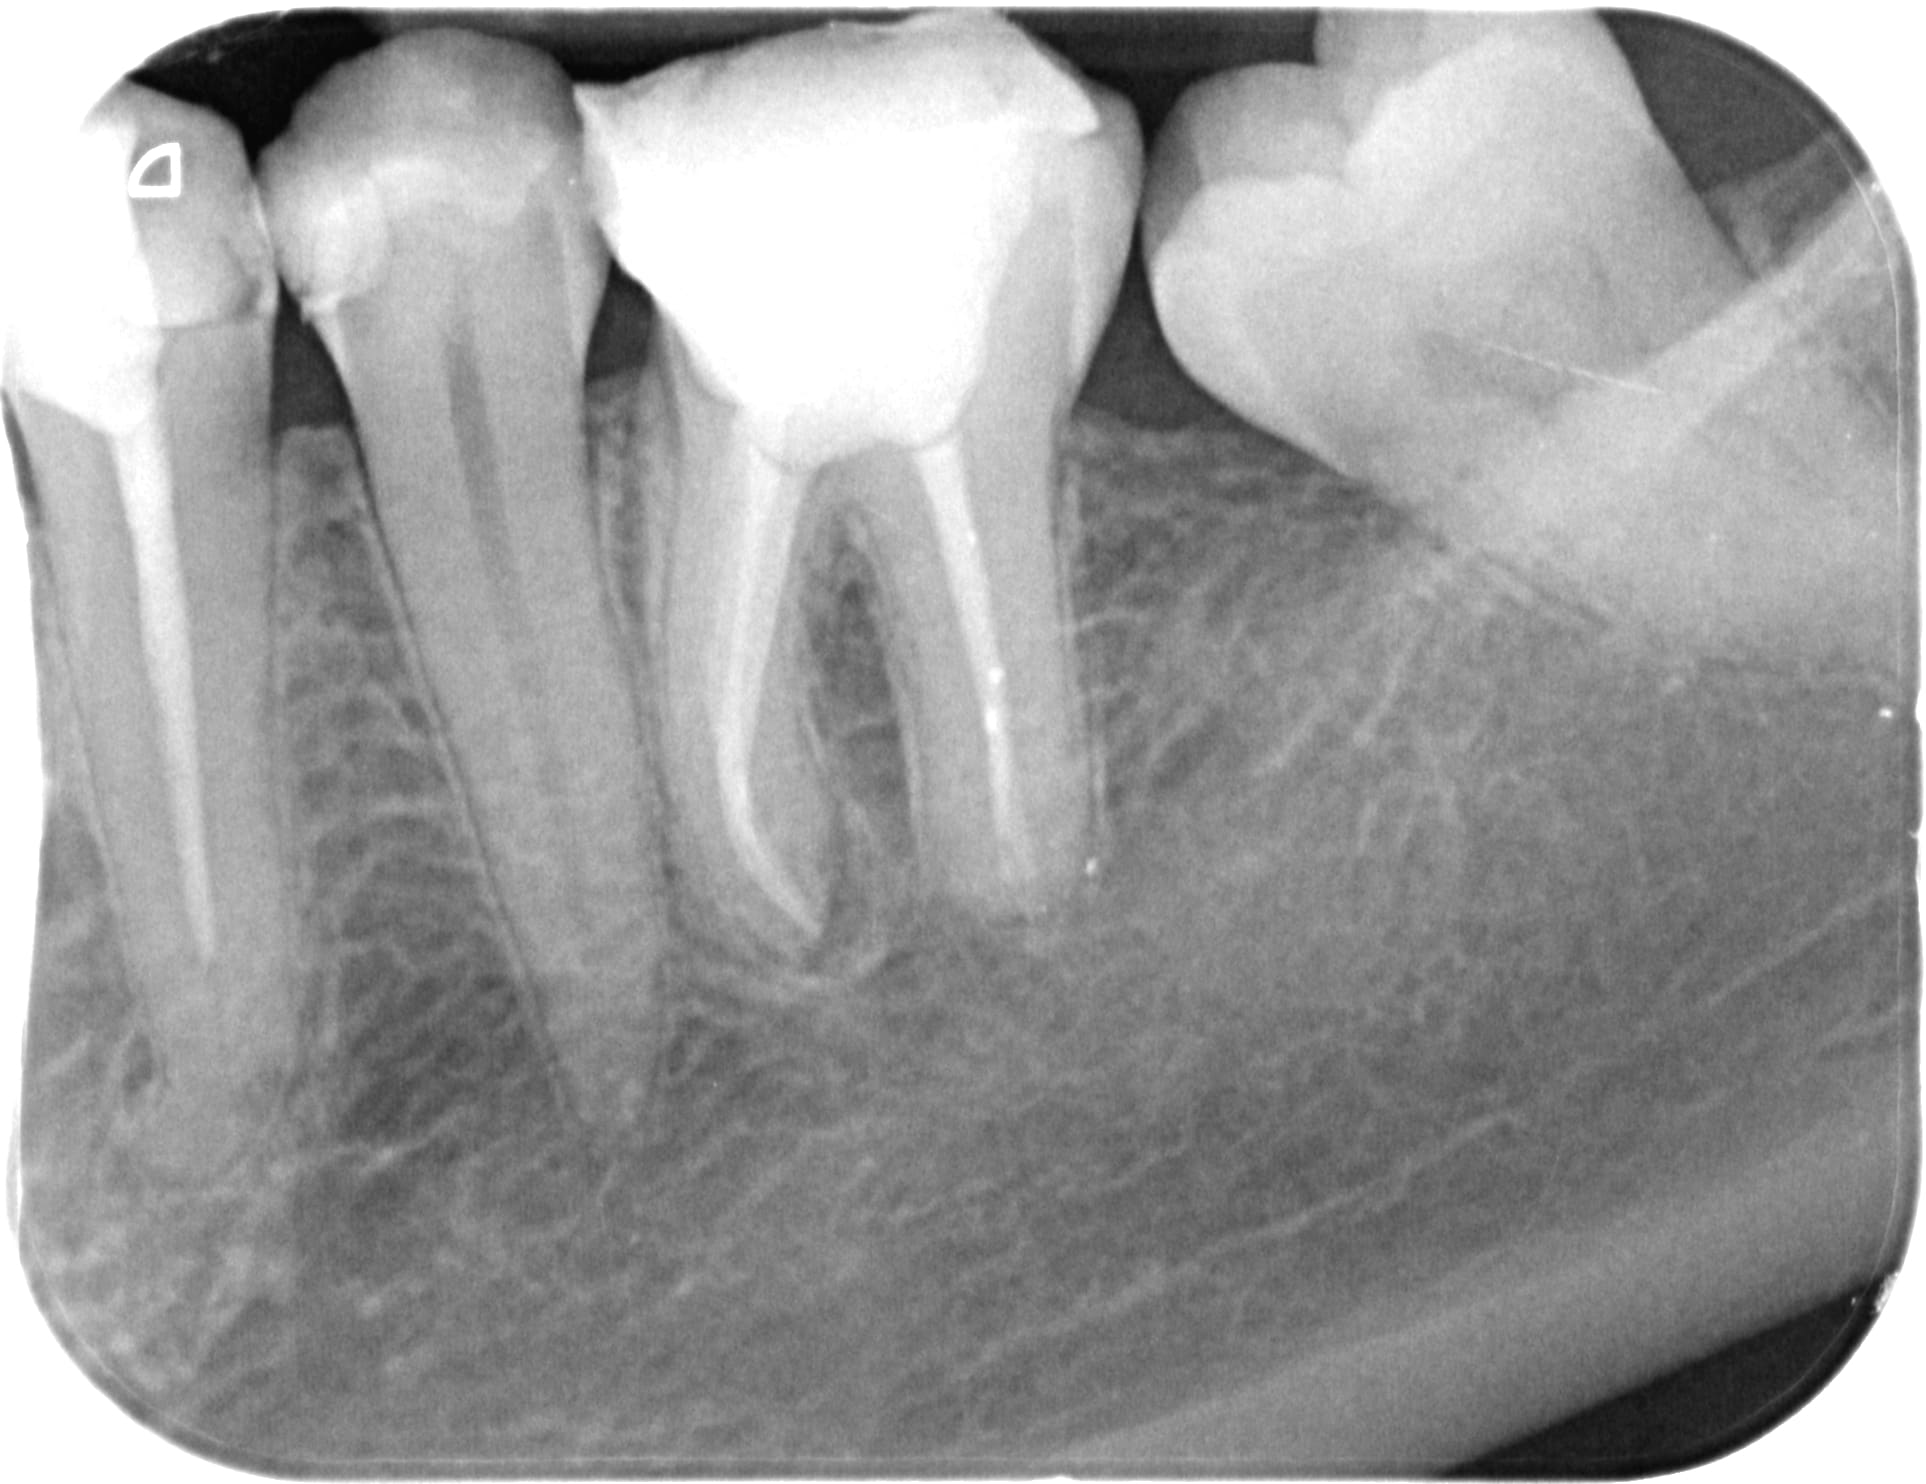

J’ai commencé une devit sur la 46 mais le soucis est que mes limes dans les disto se bloquent à 3-4mm de l’apex

Qq peut m’orienter pour arriver à l’apex?

Vu l'état du plancher, le problème n'est pas capital ....

En manuel, tu précourbes bien, tu reperes bien ta courbure avec le marquage sur le stop de ta lime.

La j'ai repris les canaux mesiaux en manuel, lime k/H en alternance... l'ancien prat avait buté dans la courbure. La difficulté c'est biensur de retrouver les canaux et surtout de na pas continuer dans la fausse route.

Bon sinon le plancher cameral fin comme un papier a cigarette en effet c'est préoccupant…